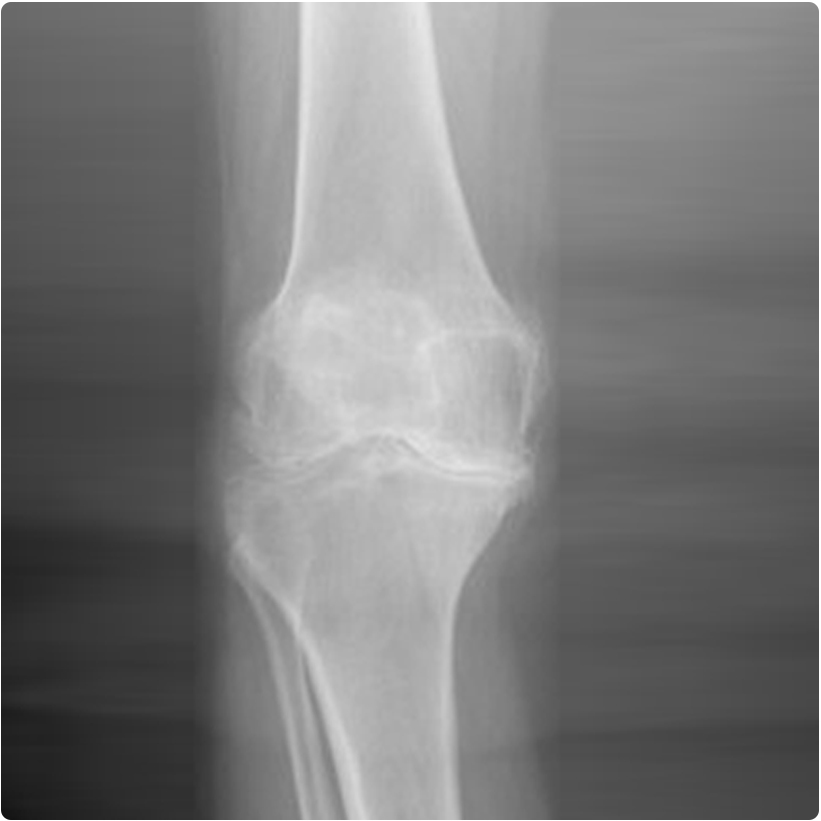

Ayrıca hastanın dizinin sadece bir bölgesi bozulduğunda, özel bazı durumlarda kullanılabilen parsiyel (kısmi) diz protezi de vardır. Resimde diz ekleminde osteoartriti olan bir hastanın ameliyat öncesi ve total (tam) diz protezi uygulandıktan sonraki diz röntgen grafileri görülmektedir.